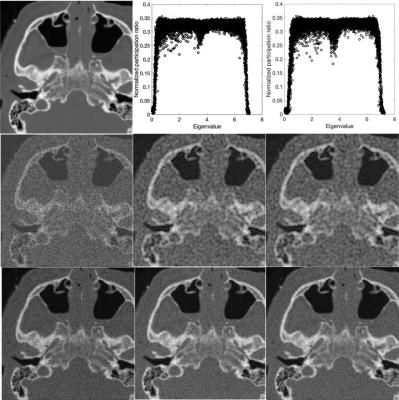

A medical image denoising method based on principles of quantum mechanics outperform machine learning, statistical methods, and neural networks. The same approach could aid quantum computing performance at scale. (Photo: Hashemi et al.)

The authors apply the same mathematics that describes the localization of particle vibrations in the surrounding physical space to decipher the localization of pixel intensity in images. In this way, they can separate the noise-free “signal” of the anatomical structures in the image from the visual noise of stray pixels.

“The main aspect was developing an algorithm that automatically separates the localized (signal) and nonlocalized (noise) components of pixels in an image by exploiting their distinct behaviors,” Hashemi said.